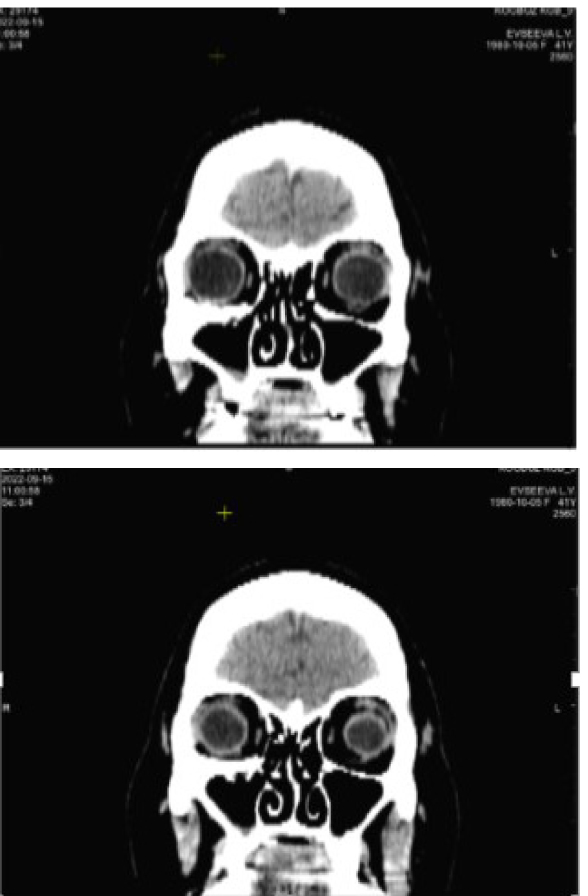

Клинический пример 2. Пациентка Б., 52 года, два года назад получила бытовую травму – ударилась головой при падении. По месту жительства была проведена ПХО ран лица, через 3 недели после травмы – реконструкция скулоглазничного комплекса. Через год после травмы выполнена реконструкция орбиты по 3D-модели.

На момент обращения объективно выявляется ретракция верхнего века, отклонение правого глаза кверху и отсутствие его подвижности книзу (рис. 5).

По результатам КТ и данным анамнеза на этапе планирования операции предположили отсутствие нижней прямой мышцы справа (рис. 6).

Пациентке поставлен диагноз: Оперированная травматическая деформация орбиты. Травматическое косоглазие. Рекомендовано хирургическое устранение косоглазия. С этой целью проведена нижняя парциальная транспозиция боковых прямых мышц в следующем объеме: от внутренней и наружной прямых мышц отделены порции в 2/5 ширины сухожилия, перемещены книзу и фиксированы в месте крепления нижней прямой мышцы. Также выполнена рецессия верхней прямой мышцы 3 мм. В раннем послеоперационном периоде отмечено уменьшение вертикальной девиации и появление подвижности книзу (рис. 7).

Рис. 6. Компьютерная томография орбит до операции. Клинический пример 2